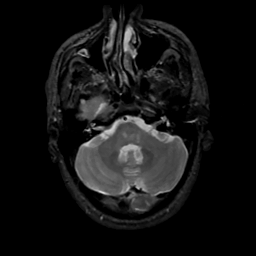

MR Study #10, April 28, 1991 -- Slice #11